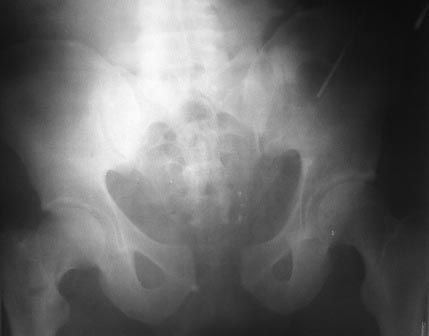

Приношу свои извинения за задержку с ответами на письма - две недели отсутствовал в отделении, не имея доступа к первоисточникам не видел смысла делиться соображениями. На форум, по моему предложению, случай представил младший коллега. Пишу об этом не с целью как-то уменьшить свою ответственность - ОПЕРИРОВАЛ Я, ТАКТИКУ ОПРЕДЕЛЯЛ Я, ПРОКСИМАЛЬНЫЙ ПЕРЕЛОМ ПРОПУСТИЛ Я... Теперь об одном обстоятельстве, которое меня не оправдывает, но может быть полезно в дальнейшей работе. В моей ошибке есть поучительный аспект: больной переведен в отделение 25.12.2013г., без снимков. На основании диагноза в выписке мы сняли таз (рис.1). Думаю, все согласятся, что картина там была, в отношении выявления перелома шейки несколько иная. В дальнейшем наше внимание занимала в первую очередь голень - высокий открытый перелом, массивная рвано-ушибленная рана мягких тканей вокруг бугристи, которая полностью не закрыта и по сегодня. Снимок, выставленный в первом сообщении, как "при поступлении" - от 15.12.2012г., т.е. сделан был при поступлении в ЦРБ. Родственники привезли его позже, мне пытались показать, но я сказал, что он уже не нужен - мы сделали свои. Думаю, что не проигнорировав его, я перелом бы заподозрил, верх переснял, не объяснял-бы себе картину после фиксации симфиза проекционным искажением.

Представляю материалы по больному на сегодня. Сделали 13.03.2013г. снимки.